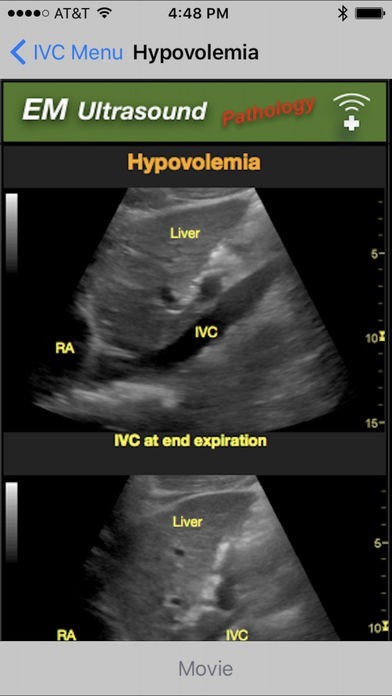

Emergency Medicine Ultrasoundのスクリーンショット

Included in this application are detailed descriptions of normal values and techniques for obtaining images, as well as photo and video examples of normal and pathological exam findings.